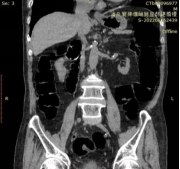

检测方法:常规准备,取左侧卧位肛门插管,缓注碘造影剂稀释液约100ml(碘剂∶生理盐水=1∶2),见阴道有液体流出,行俯卧位盆部扫描,将断层图像原始数据进行多平面重建(MPR)、三维重建(3D),展示瘘管形态。

3D图像:直肠(黄色箭头)、阴道(白色箭头)

瘘管(红色箭头)